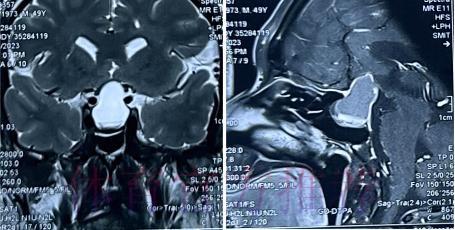

在高速对抗的现代足球里 现场肉眼和赛后情绪往往会放大对伤情的判断 一名球员倒地呻吟或无法坚持比赛 很容易被解读为韧带断裂 或肌肉严重撕裂 但真正决定恢复周期的关键因素 通常要到核磁共振检查之后才会明朗 因为核磁能在较早阶段清晰显示软组织 肌肉 韧带以及骨结构的微小损伤情况 对伤情做出更接近真相的分级判断 塞巴略斯此次就是典型案例 初步观感可能让人联想到更严重的伤病 但核磁提示伤情相对可控 没有出现完全断裂或大面积撕裂 也就意味着他不需要漫长的康复旅程 只要遵循医学建议 科学负荷管理 就有机会用较短的时间重新回到训练场和比赛中

足球历史上 不乏因为伤情评估偏差而延误治疗的例子 某些球员在初诊时被认定为普通拉伤 结果因为没有进行完整的核磁共振检查 继续带伤出战 最终发展成严重撕裂 被迫长时间缺阵 从竞技层面来看 一次错误判断 可能直接改写一个赛季的走向 也可能在球员的职业生涯里留下不可逆转的隐患 与这些案例对照 塞巴略斯这次的过程显得更为规范 受伤后迅速接受医学影像检查 医疗团队根据结果评估伤情等级 给出清晰恢复计划 俱乐部层面则通过官方渠道适度释出消息 在 保护隐私与满足公众关切之间 取得平衡 对比之下 可以看出 现代职业俱乐部在伤病管理上的专业程度 已远超十几年前更多依赖经验和肉眼判断的时代 同时也提醒公众 不要被比赛画面中的瞬间表现完全左右 而是学会等待更权威的医学信息